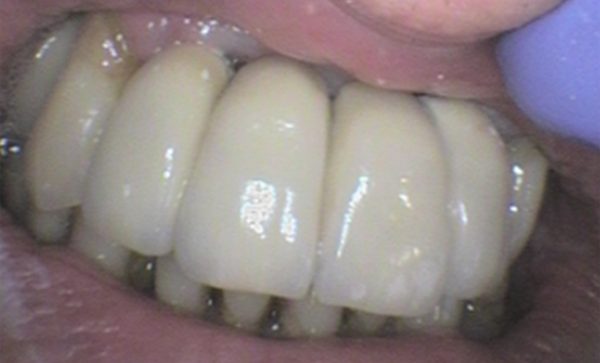

Case 9